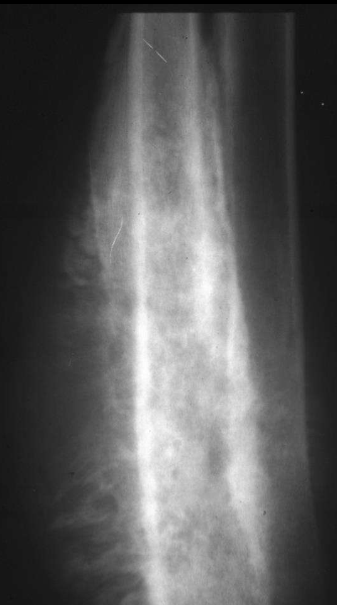

Permeative lysis

Permeative lysis and a fracture